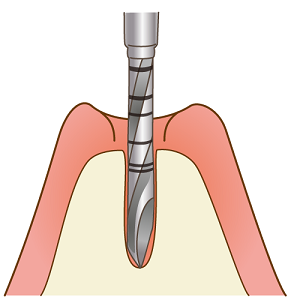

一次手術

インプラントの方向・深さを事前に検査した部分にマーキングします。

インプラントを入れる穴を専用のドリルで開けます。